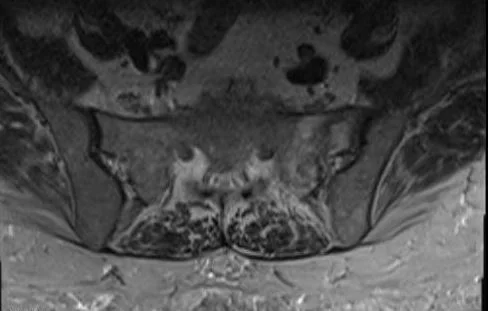

A 61 y.o. woman on steroids for COPD comes in with back pain; she is sent in to rule out cauda equina.

this is her MRI. What does she have?

Our patient has a sacral insufficiency fracture.  This is a stress fracture of the sacrum and is a common cause of low back pain in the elderly with osteoporosis who do not experience trauma.   Bone scan and MRI are the most sensitive means of detection. Patients are managed conservatively  with bed rest and rehabilitation. More recently, sacroplasty( a minimally invasive procedure similar to vertebroplasty)  has emerged as an alternative therapy.  The sacral insufficiency fracture is found in the sacrum parallel to the SI joint.

The fractures can form an H across the body of the sacrum

Patients present with low back pain and sacral radiculopathy mimicking cauda equina syndrome.  Pain is often in the buttock , hip, or groin not necessarily over the sacrum. They are often associated with pubic rami fractures.